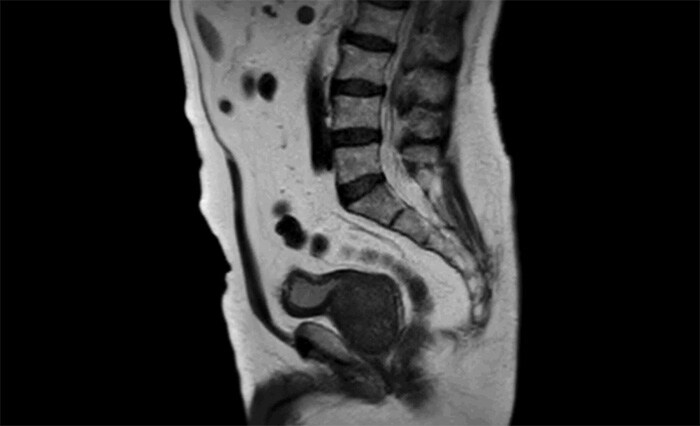

Цель: Разработка и внедрение в клиническую практику методики исследования перфузии простаты без артефактов движения. Описание проекта: Согласно опыту ОКДЦ Ростова-на-Дону, наиболее информативными в клинических исследованиях простаты являются Т2-взвешенные и DWI-взвешенные изображения высокого разрешения. В то же время, информативность исследования может быть увеличена при использовании исследования перфузии предстательной железы с динамическим контрастным усилением. Однако, артефакты движения значительно затрудняют интерпретацию полученных данных. Разработка методик динамического сканирования, свободных от артефактов движения, может значительно увеличить диагностическую чувствительность исследования. Результаты: Разработаны протоколы сканирования простаты с использованием ускоренных методик частичного заполнения k-пространства: k-t SENSE [1] и 4dTRAK Viewsharing [2], которые малочувствительны к артефактам движения, а также режим с использованием респираторного навигатора для контролем движения простаты. Проведен сравнительный анализ данных перфузии, полученных при помощи различных методик (Рис. 2).

K-t SENSE

4dTRAK Viewsharing

DCE с Навигатором